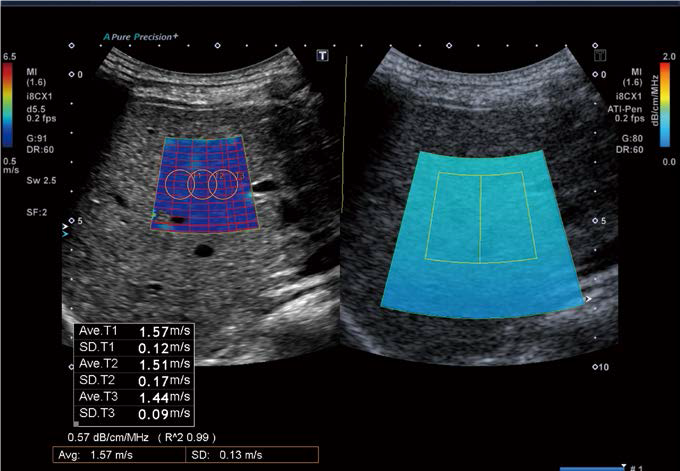

ROI вимірювання встановлюється на глибині від 4 до 7 см, приділяючи особливу увагу тому, щоб ROI вимірювання не містило жодних артефактів реверберації чи акустичних тіней. Ми продовжуємо збирати дані та виконуємо постійний статистичний аналіз, щоб оцінити кореляції між середніми значеннями, отриманими за допомогою двох систем. Початкові дані, зібрані на сьогоднішній день у 57 суб'єктах, показують хороші результати кореляція між значеннями, отриманими за допомогою Aplio a, і значеннями, отриманими за допомогою Aplio i800 (рис. 2).

Дані люб'язно надані д-ром Масахіро Огава

Рис.2 Порівняння значень ATI, отриманих за допомогою Aplio i800 і Aplio a

Це надзвичайно корисно для оцінки тяжкості фіброзних змін, що є основним фактором у визначенні прогнозу пацієнтів із захворюваннями печінки (рис. 3).

Коли ожиріння печінки прогресує до цирозу, кількість жиру фактично зменшується, що може помилково вважатися ознакою клінічного поліпшення. Ось чому важливо оцінити жорсткість тканини печінки за допомогою SWE. У Aplio a ATI (для вимірювання жирових змін) і SWE (для вимірювання фіброзних змін) можна виконати за допомогою однієї кнопки, і немає необхідності змінювати датчики.

Цей метод візуалізації, відомий як Advanced SWE, є оригінальною технологією, розробленою Canon,  яка дозволяє одночасно оцінювати жирові та фіброзні зміни в цільовій області (рис. 4).